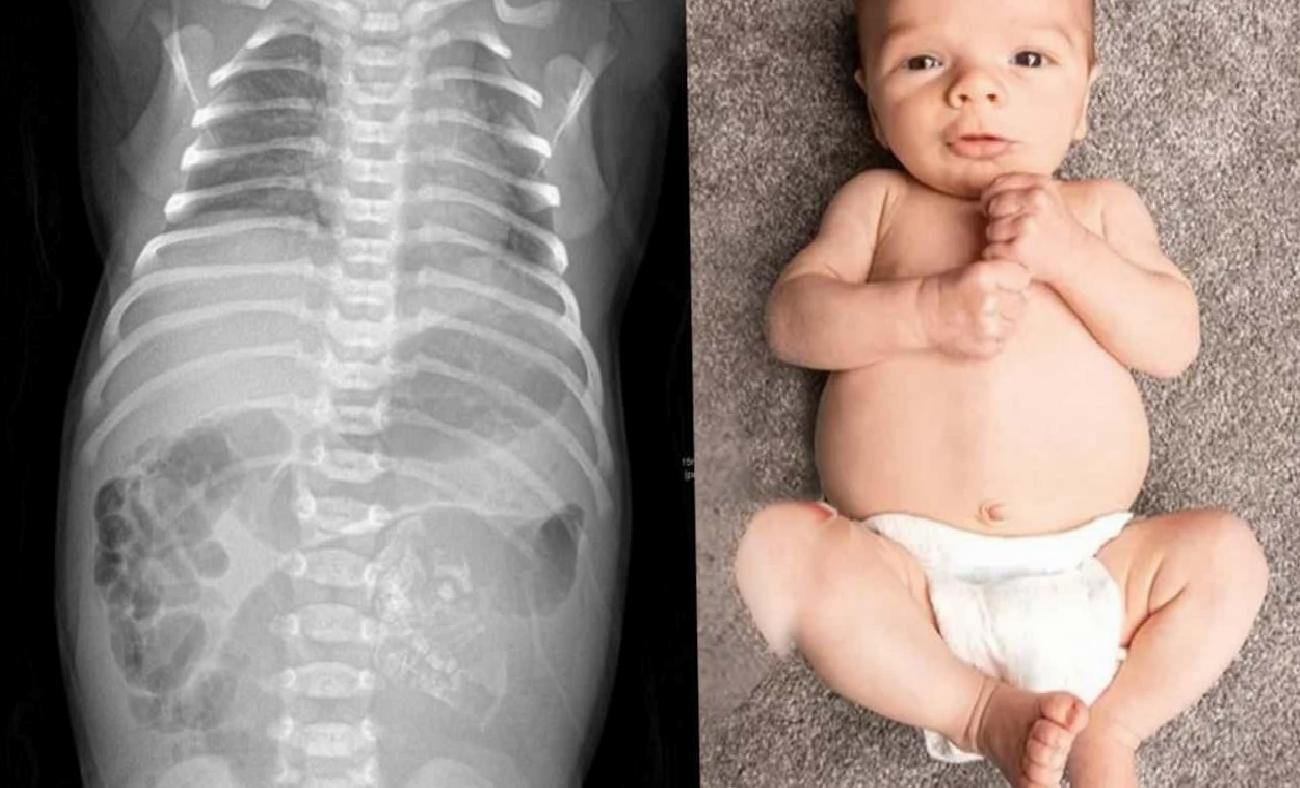

Hindistan’da 32 yaşındaki bir kadın, tıp tarihine geçecek oldukça sıra dışı bir doğum gerçekleştirdi. Kadının dünyaya getirdiği bebek, karnında gelişmemiş ikiz kardeşinin fetüsü ile birlikte geldi. Bu durum, hem sağlık alanında hem de toplumda büyük bir şaşkınlık yarattı. Modern tıbbın sağladığı ilerlemelere rağmen, bazı durumlar hala doktorlar tarafından tam olarak açıklanamıyor. İşte bu nadir olay da tıp dünyasının en ilginç vakalarından biri olarak kayıtlara geçti.

Hindistan’da dünyaya gelen bebek, karnında taşıdığı ikiz kardeşinden ayrı olarak, doktorların başarılı müdahalesi sayesinde sorunsuz bir şekilde kurtarıldı. Operasyonun ardından bebeğin sağlık durumunun iyi olduğu bildirildi. Uzman Dr. Prasad Agarwal, bu durumu değerlendirirken, “Bu, dünyanın en nadir vakalarından biri” ifadesini kullandı.

Bilimsel literatürde ‘Fetus in fetu’ olarak adlandırılan bu durumun benzerlerine oldukça nadir rastlandığını belirten uzmanlar, geçmişte kaydedilen benzer vakaların sayısının 200 civarında olduğunu ifade ediyorlar. Bu tür durumların tıbbi açıdan incelenmesi ve anlaşılması, sağlık bilimleri alanında önemli bir gereklilik olarak öne çıkıyor.